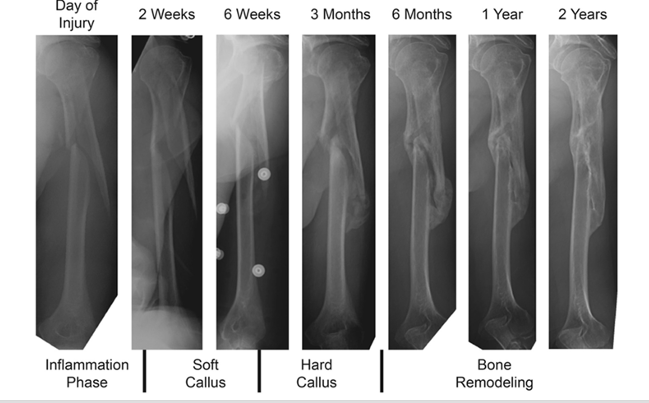

Describe the mechanism of bone healing after a fracture [5]

Fracture hematoma:

* Blood from broken vessels forms a clot 6-8 hours after injury

* Creates hypoxia; low pH

* Dead cells present cause pro-inflam cytokines

* Swelling

Fibrocartilaginous callus

* Angiogensis occurs (due to previous hypoxia)

* Fibroblasts and osteogenic precursors invade procallus

* Chondroblasts makes fibrocartilage

Inflammatory, granulation and soft callus

* Organisation and resorption of clot as new capillaries form

* Fibroblasts enter and differentiate as chondrocytes

* Chondrocytes produce collagen that bridges fracture site cartilage and trabecular bone laid down

Bony callus

* osteoblasts make woven bone

* Excess bone can form and create a bridge or a pseudo-arthrosis especially in the foot

Bone remodelling

* Osteoclasts remodel woven bone into compact bone and trabecular bone

* Often no trace of fracture line on X-rays.